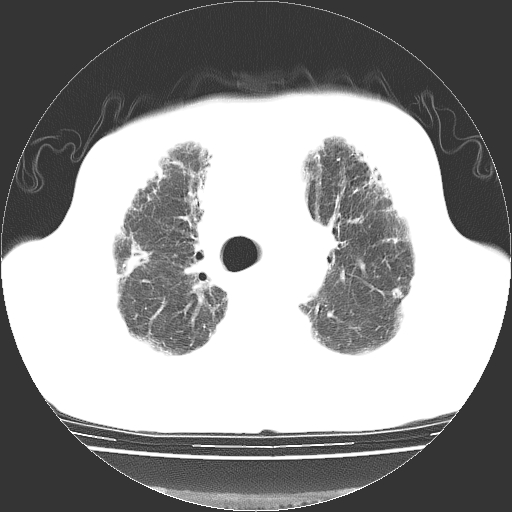

标题: CT25149:男,69岁,反复咳嗽、咳痰五年余,呼吸困难三天。 [打印本页]

男,69岁,反复咳嗽、咳痰五年余,呼吸困难三天。

慢支伴感染、肺气肿、肺心病

慢支伴感染、肺气肿、肺心病!支持!另:间质纤维化!

两肺间质性炎症并感染,左上叶肉芽肿

考虑慢性间质性肺炎并肺间质纤维化。

慢支伴感染、肺气肿、肺心病。双肺间质性改变(间质纤维化)。